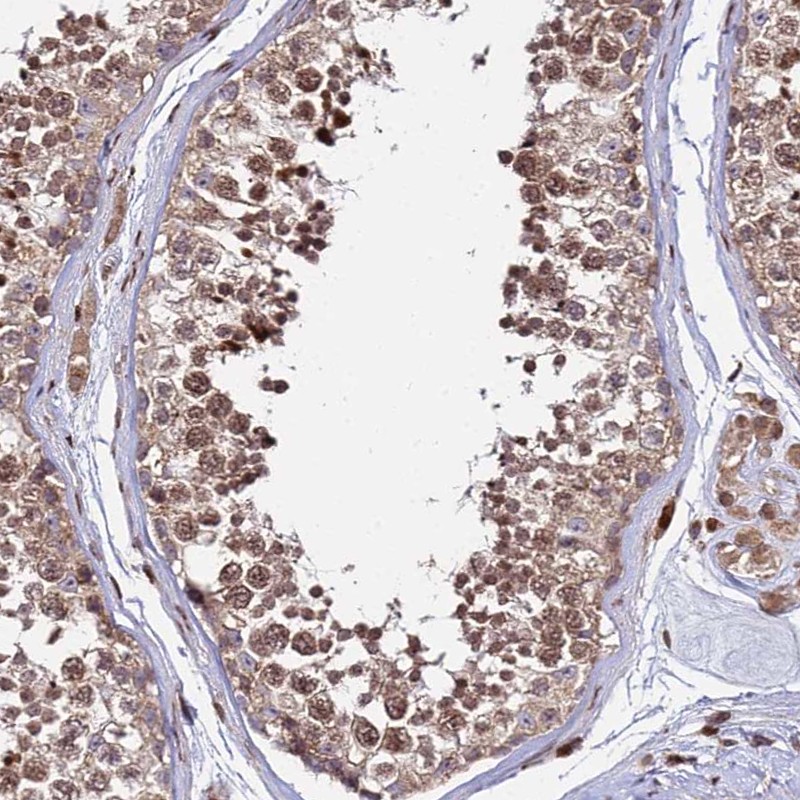

Immunohistochemical staining of human testis shows moderate nuclear and cytoplasmic positivity in cells in seminiferous ducts.